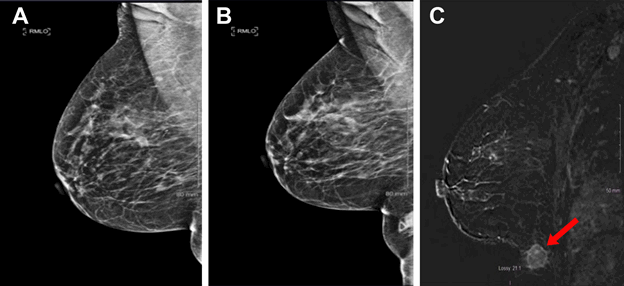

A 59-year-old G3P3 post-menopausal female with a past medical history of hypertension presented to her primary care physician for routine checkup and noted a lump inferior to her right inframammary fold. She described the lump as presenting for longer than one year but had been progressively enlarging. She was referred for an ultrasound of the area which demonstrated a 25 mm x 16 mm x 18 mm lobulated mass. Mammography performed at the same time with an attempt to image the area of concern showed a density corresponding to the palpable area of concern that was not appreciated on previous examinations since it was not in the field of view (Figure 1A and Figure 1B). A core needle biopsy of the mass was performed under ultrasound guidance, and pathologic analysis showed invasive ductal (IDC), which was estrogen receptor (ER)-negative and progesterone receptor (PR)-negative, and HER2-positive. Given other benign findings on mammography, a breast MRI was performed (Figure 1C), which demonstrated a second, 8 mm spiculated nodule inferior and lateral to the previously biopsied mass along the abdominal wall. This mass also underwent ultrasound-guided core needle biopsy, which demonstrated ER-negative, PR-negative, and HER2-positive IDC.

Figure 1. Mammogram six months before A) and after B) patient presented with a complaint of an enlarging chest wall mass with a skin marker (triangle) placed over the palpable tumor; the mass is best seen on MRI (C, arrow)